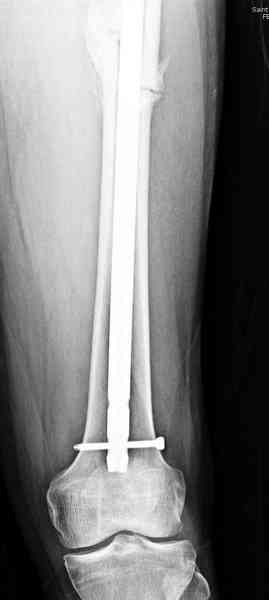

В первый же день произведено антеградное штифтованием DePuy Trochanteric Nail.

На второй день (7) обнаружен пропущенный перелом,

и проведены шурурпы через и спереди штифта без удаления.

Послеоперационные снимки